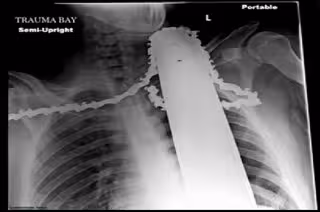

Un joven estadounidense de 21 años se ha incrustado la motosierra en el cuello y en el hombro con la que estaba podando un árbol. Se ha salvado por apenas un centímetro.

La hoja penetró en su cuello y en su hombro. Los equipos de emergencia cortaron el motor pero dejaron la hoja en el cuerpo para evitar que se derramara más sangre, y así llegó al hospital, según publica el diario 'Daily Mail'.

La doctora ha comentado que "afortunadamente todo ha quedado en el músculo, tejidos blando y la piel". Si la motosierra hubiese traspasado un centímetro más -la distancia a la que ha quedado de la arteria carótida- el resultado no habría sido el mismo.